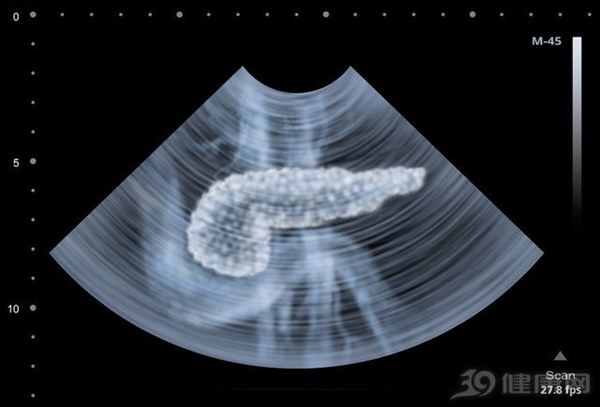

Ngay cả chuyên gia điều trị bệnh ung thư như bác sĩ Vương Lỗi cũng không phát hiện ra rằng sự khó chịu của bản thân có liên đến ung thư tuyến tụy. Điều này là do ung thư tuyến tụy nằm sâu trong bụng, phía sau ruột và các cơ quan nội tạng không nhạy cảm với đau như bề mặt cơ thể, vì vậy ung thư tuyến tụy giai đoạn sớm hầu như không có triệu chứng và không dễ phát hiện.

Vị trí tuyến tụy ẩn sâu trong bụng nên rất khó phát hiện triệu chứng